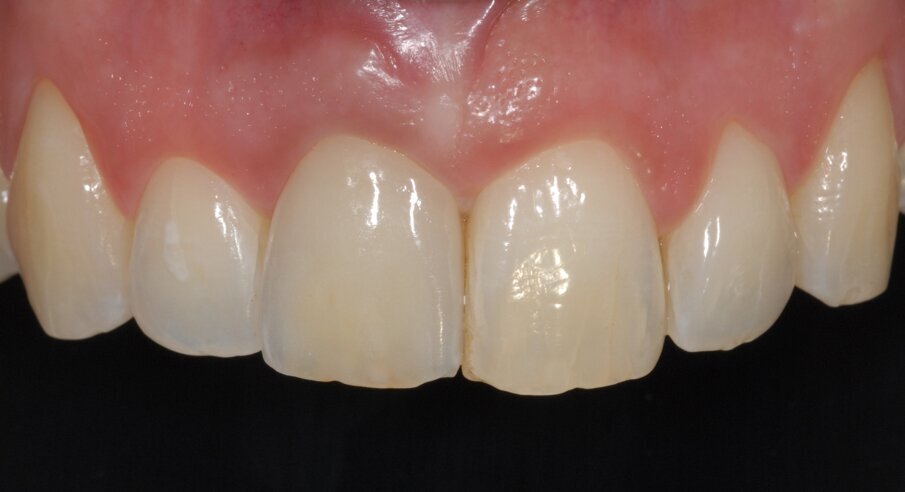

Alla paziente è stato chiesto di evitare di masticare sull’area trattata per 3 mesi e di evitare di lavarsi i denti per le prime 2 settimane. È stato prescritto un risciacquo con clorexidina allo 0,12% (Eburos, Dentsply) per 2 settimane. Successivamente, sono stati consentiti lo spazzolino convenzionale e il filo interdentale. La paziente ha mantenuto il provvisorio per 12 mesi, quindi è stata presa un’impronta, secondo la metodica di Hinds16 (Fig. 5). È stata, quindi, realizzata e avvitata sull’impianto una corona in zirconia-ceramica con moncone individualizzato (Figg. 6, 7).

Fig. 6 - Corona defi nitiva in zirconia ceramica avvitata sull’impianto. Il profi lo d’emergenza è assolutamente simile a quello dell’elemento adiacente.